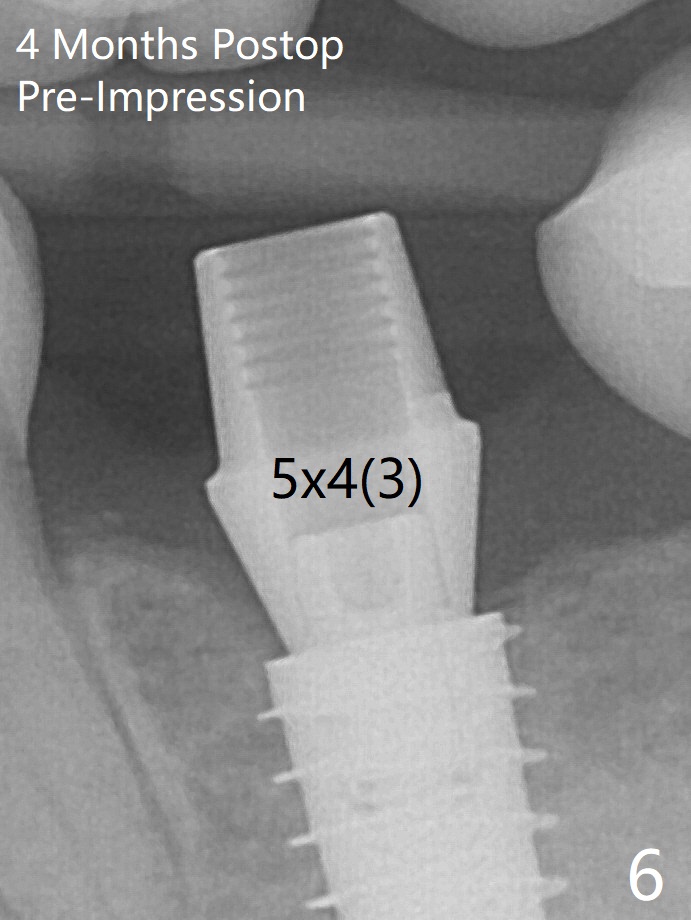

In contrast to #2 implant, the insertion torque of a 5x9 mm implant at #18 (Fig.1) is less than 10 Ncm because of depth difference between 2 implant systems. The design is for 5x10 mm. In fact each drill has its inherent 1.2 mm long tip. The 8.5 mm drilling depth is enough for 9 mm implant. The 2nd potential problem is that the implant may truncate a branch from the Inferior Alveolar Canal to the distal root of the 1st molar (Fig.2 (original design)). Ideally the implant should be placed distal and tilted mesial and short in length (Fig.3 (design to be improved)). A smaller implant may also help. A layer of new bone forms on the top of the implant 3 months postop (Fig.4 *). It is removed with surgical handpiece. After use of 5.6 mm profile drill, a 6x4 mm healing abutment is placed with minimal clearance from the mesial crest (Fig.5 *). A month later, a 5x4(3) mm pair abutment is seated apparently completely (Fig.6). A crown is delivered nearly 6.5 months postop (Fig.7 (mesial contact light)). The implant is subcrestal (*).